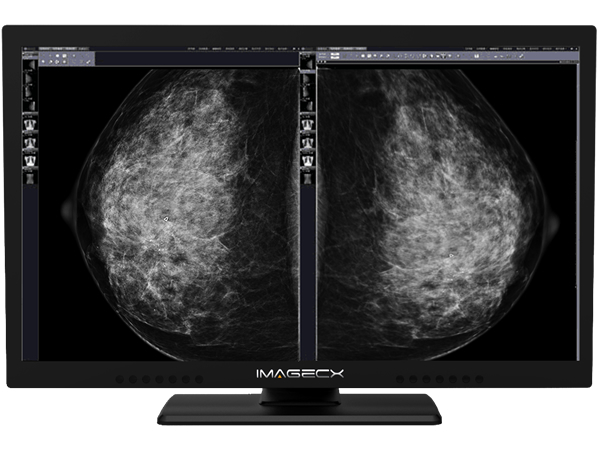

8M一體化雙屏醫用顯示器

產品分類:8MP彩色雙屏醫用顯示器

屏幕尺寸:31.5英寸

分辨率:3840×2160

產品介紹:具有八百萬像素分辨率,超高亮度,超高對比度,寬視角。

在整個壽命期內保持穩定并能夠進行持續的DICOM校準,內置16bit LUT,符合醫療影像高精度需求。

在同一臺顯示器上實現雙屏顯示功能,保證醫療圖像對比一致性,可適用于所有醫療影像顯示,不會成為過渡產品(4K×2K是顯示領域主流)。